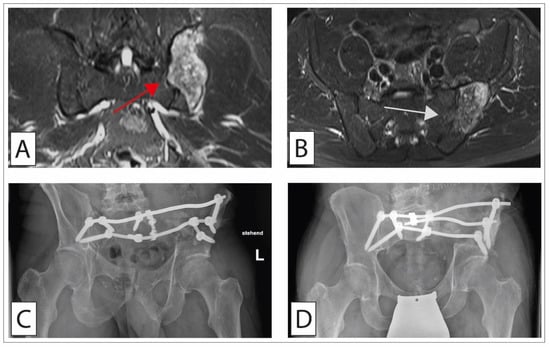

- Pelvic Ring Reconstruction Using Double-Barreled Free Vascularized Fibula Graft (FVFG)

4.2.3. Surgical Treatment of Chondrosarcoma of the Pelvis

4.2.4. Radiotherapy